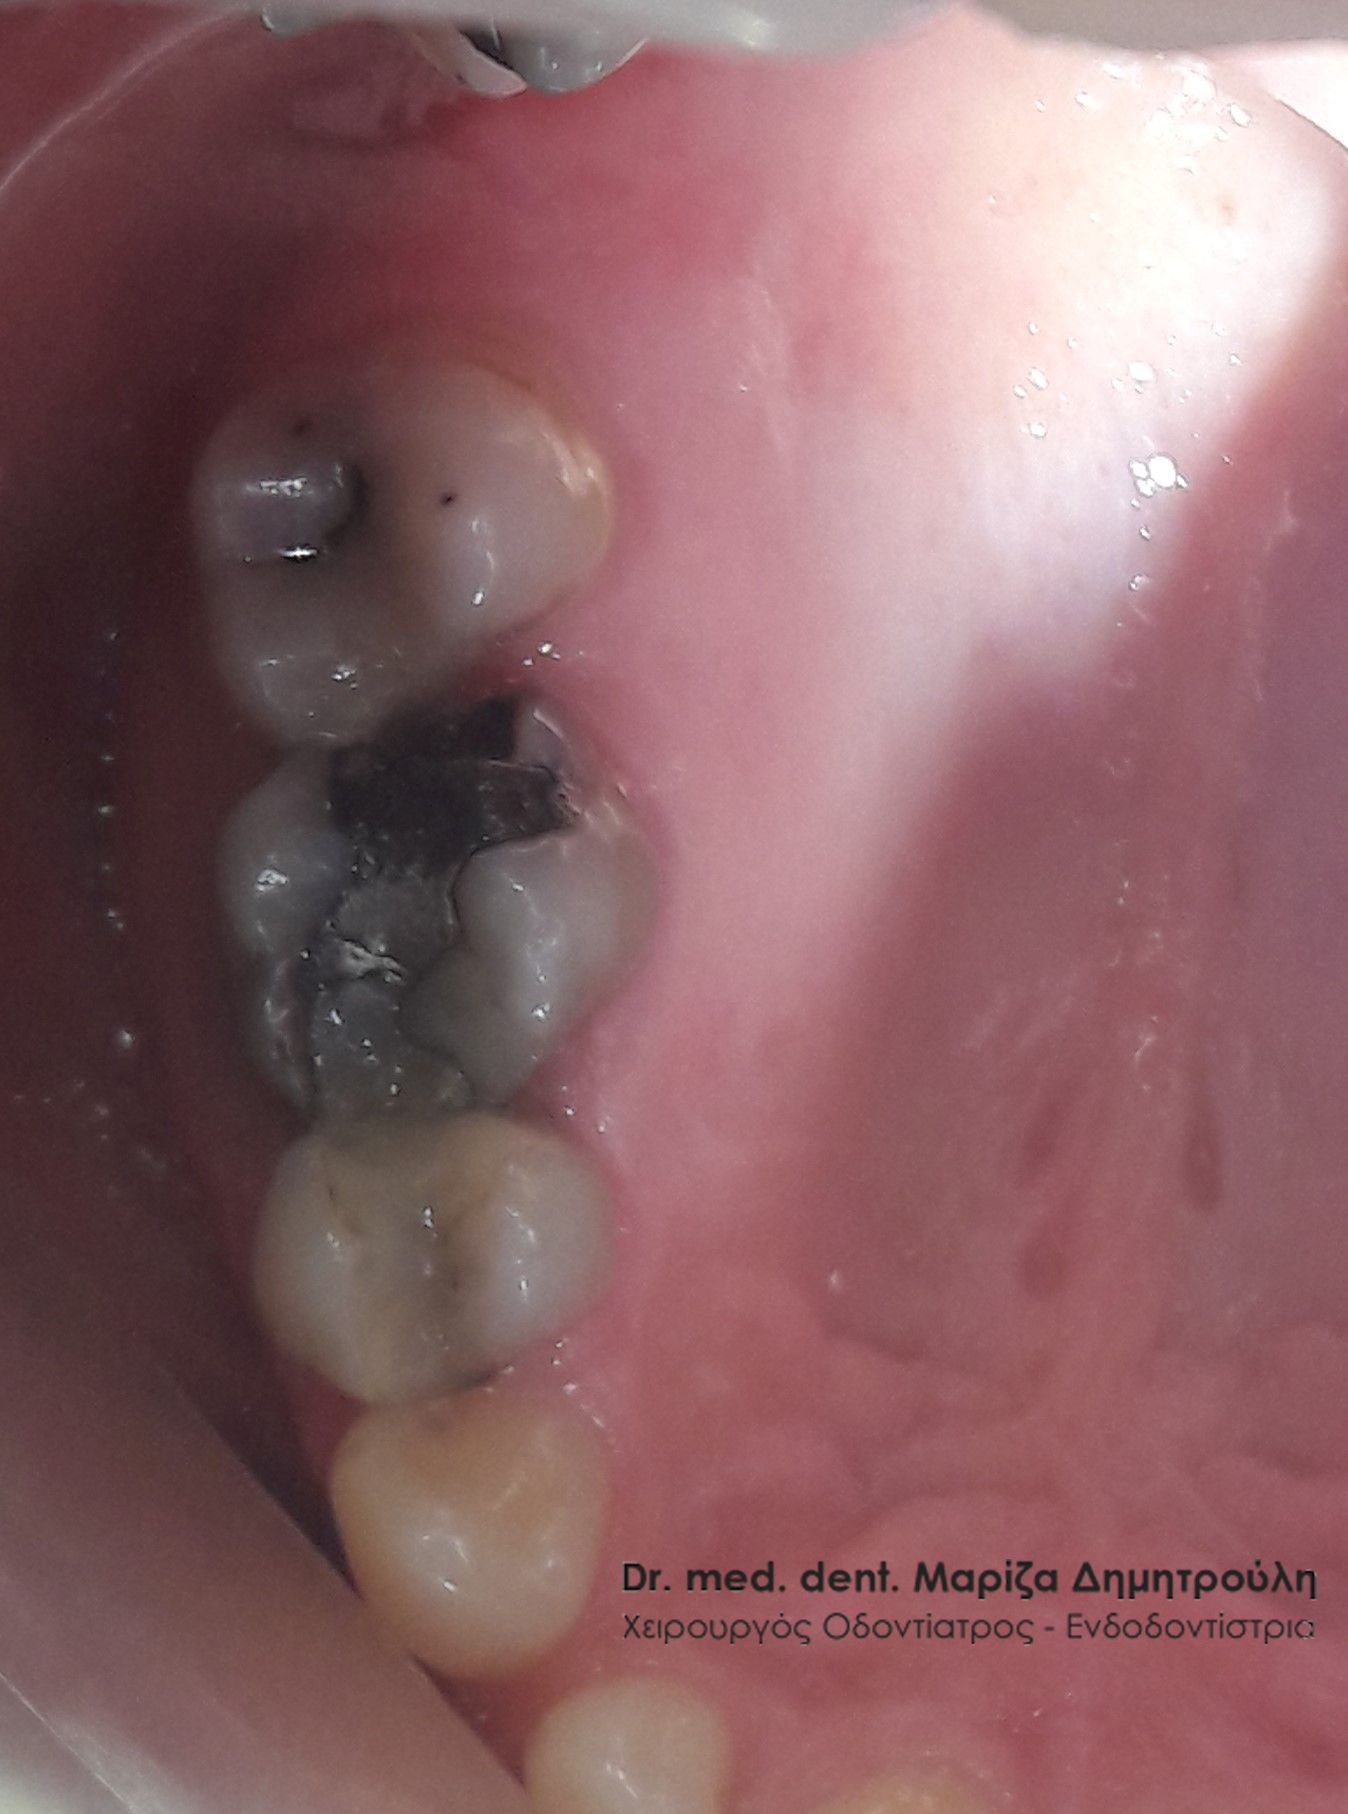

Η ασθενής επισκέφτηκε το ιατρείο καθώς ο πρώτος κάτω δεξιός γομφίος την πονούσε περιοδικά. Μετά την κλινική εξέταση διαπιστώθηκε ένα παλιό μεγάλο σφράγισμα αμαλγάματος, του οποίου τα όρια δεν είχαν επαφή με το δόντι και είχαν δημιουργηθεί κενά μεταξύ του μαύρου σφραγίσματος και οδοντικών τοιχωμάτων. Αποφασίστηκε η αντικατάσταση του παλιού σφραγίσματος με νέο λευκό σφράγισμα σύνθετης ρητίνης.

Η μεσαία φωτογραφία δείχνει την το έλλειμμα του δοντιού μετά την αφαίρεση του σφραγίσματος αμαλγάματος και των τερηδονισμένων οδοντικών ιστών. Στη δεξιά φωτογραφία φαίνεται η τελική αποκατάσταση του δοντιού.

ΠΡΙΝ

Εικόνα του δοντιού μετά την αφαίρεση του παλιού σφραγίσματος και της τερηδόνας

META